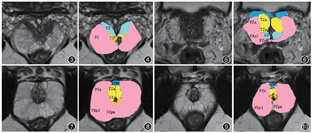

前列腺外周带是年轻男性前列腺的主要腺体成分,占腺体组织的约70%。在前列腺成像报告和数据系统第2.1版(prostate imaging reporting and data system v2-1,PI-RADS v2.1)中前列腺外周带细分为3个部分(后内区、后外区和前区),位于中线两侧的腺体的底部、中间和尖部(图1, 2, 3, 4, 5, 6, 7, 8, 9, 10)[2]。两侧的外周带前部显示为2个角,因此被称为前角。在尖部,2个前角向前内弯曲,在尿道前方彼此邻接,形成围绕尿道的外周带环。在中部腺体,外周带位于后部、外侧部和大部分前外部[3, 4]。前角向前内侧弯曲,但不相互接触。在底部,外周带环绕中央带和移行带。前角较少向前伸展。中央带占据大部分的前列腺后内侧部。在MRI中,正常前列腺外周带表现为高T2信号,可以容易地与周围其他结构区分开来[3, 4, 5, 6]。

移行带位于前列腺中部和底部的前内侧,包绕近端尿道。在年轻成年人中,TZ构成前列腺腺体组织的5%,表现为均匀的低T2信号。接受前列腺MRI检查的大多数受检者具有一定程度的前列腺增生,因此,移行带的表现与以上典型描述有很大差异。

前列腺中央带是扁锥形腺体组织,围绕射精管,在前列腺底部突出,其尖端位于精阜,占年轻成人的前列腺的25%。35岁后中央带体积逐渐减小。中央带在T2WI上表现为均匀的低信号和低表观扩散系数(apparent diffusion coefficient,ADC)。前列腺区带解剖的知识和中央带的识别非常重要。

对于前列腺解剖分区,PI-RADS v2.1新规范建议使用标准化的前列腺解剖分区图。前列腺在6分部(右基部、右中部、右尖部、左基部、左中部和左尖部)基础上进一步细分为6个带,即前纤维肌肉基质带、前移行带、后移行带、前外周带、后内外周带和后外外周带。前带和后带的界线为水平方向线。内侧和外侧带的界线为沿着外周带和移行带的连接处前后方向的线。PI-RADS v2.1版前列腺分区图中,前列腺采用41个区,38个区用于前列腺、2个区用于精囊、1个区用于膜性尿道,新增前列腺底部外周带右后内侧区和左后内侧区。